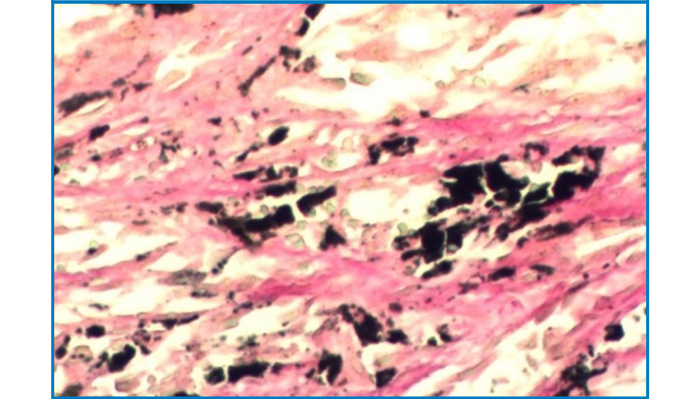

Melanin Stain

(Ferrous sulfate staining method)

Intended for staining examination of histological melanin.